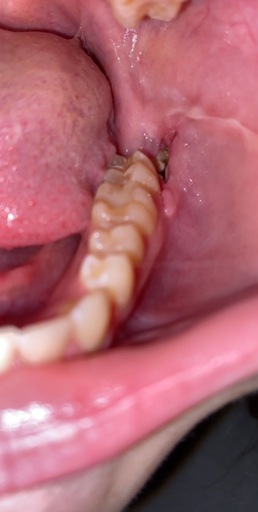

Number 30 molar

This tooth has had a root canal and a crown installed several yrs, ago. Now my dentist says the ex ray shows that the root has now separated and one side broke, therefore the tooth should be removed. Is that correct? I would then have to get a bridge or implant, or just have an empty space. I have all my other teeth except the 4 wisdom teeth. I don't like this situation. Any other possibility?